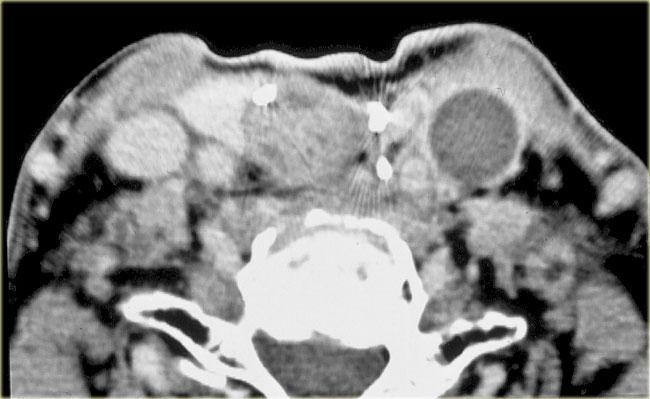

U mỡ

Bên trái là hình ảnh của một bệnh nhân có sưng nề ở phía sau bên trái cổ.

Hình ảnh MRI tại mức xương móng.

Tổn thương nằm trong khoang cổ sau.

Trong trường hợp này, việc phân tích các thành phần giải phẫu bình thường của khoang cổ sau có thể được rút gọn.

Khối có tín hiệu tương đương mô mỡ trên chuỗi xung T1W và tín hiệu bị xóa hoàn toàn khi áp dụng kỹ thuật xóa mỡ.

Không có hình ảnh ngấm thuốc (không trình bày), do đó có thể kết luận đây là u mỡ.

Bên trái là hình ảnh chuỗi xung T1W và T2W của một bệnh nhân khác có u mỡ.